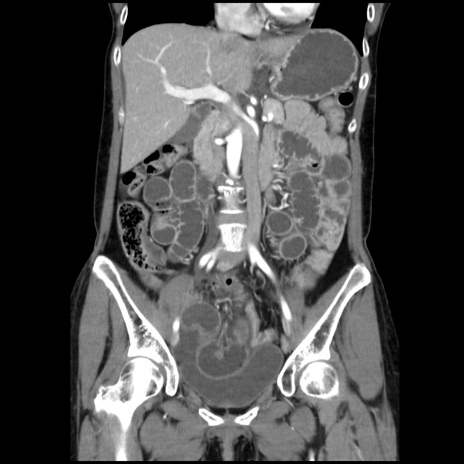

症例32(冠状断像)

【症例】40歳代 女性

【主訴】上腹部痛、嘔気・嘔吐

【現病歴】約9時間前頃から急に上腹部痛、嘔気、嘔吐が出現。改善しないため救急要請。

【既往歴】子宮頚癌(広汎子宮全摘術、放射線療法)、腸閉塞

【身体所見】腹部:平坦、軟、腸雑音亢進、上腹部を中心に腹部全体に圧痛あり。

【データ】WBC 8400、CRP 0.03